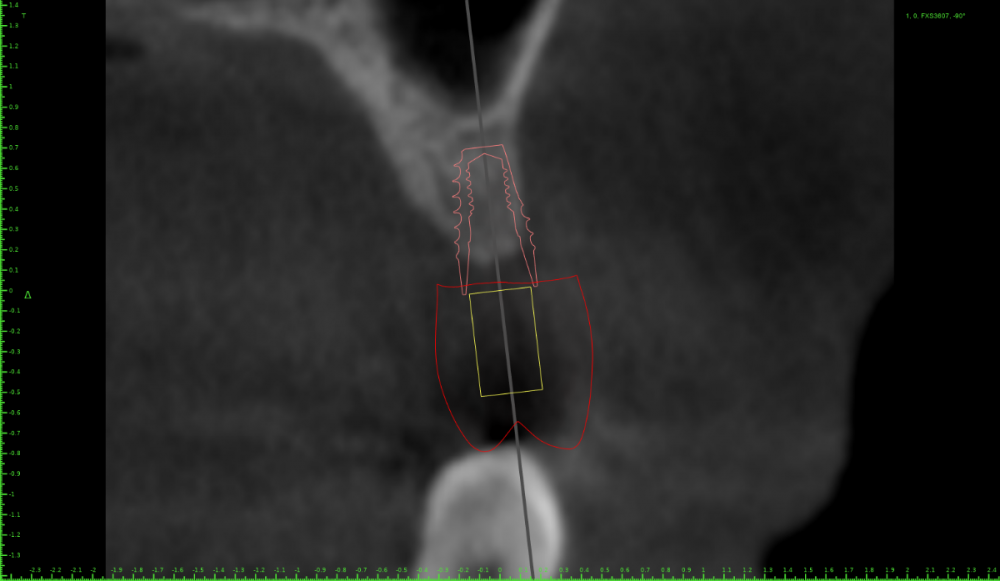

red_butler Опубликовано 28 марта, 2021 Поделиться Опубликовано 28 марта, 2021 22 часа назад, Женька сказал: Коллеги, всегда задаюсь вопросом что делать в таких случаях? формировать ложе остеотомами или эспандерами Ссылка на комментарий

Женька Опубликовано 28 марта, 2021 Поделиться Опубликовано 28 марта, 2021 7 часов назад, red_butler сказал: формировать ложе остеотомами или эспандерами но не единственный вариант же? Ссылка на комментарий

Женька Опубликовано 30 марта, 2021 Поделиться Опубликовано 30 марта, 2021 28.03.2021 в 13:15, red_butler сказал: формировать ложе остеотомами или эспандерами что то даже 3.6 на 7 (с 1.5мм полированной шейкой) с эспандерами мне кажется без нкр не обойдётся. Ссылка на комментарий

red_butler Опубликовано 1 апреля, 2021 Поделиться Опубликовано 1 апреля, 2021 30.03.2021 в 20:59, Женька сказал: что то даже 3.6 на 7 (с 1.5мм полированной шейкой) с эспандерами мне кажется без нкр не обойдётся. заглубить с проведением ЗСЛ у все пройдет 1 1 Ссылка на комментарий

Доктор Хаус Опубликовано 1 апреля, 2021 Поделиться Опубликовано 1 апреля, 2021 (изменено) 31.03.2021 в 00:59, Женька сказал: что то даже 3.6 на 7 (с 1.5мм полированной шейкой) с эспандерами мне кажется без нкр не обойдётся. Если Вы правильно выбрали форму зуба, то в вашей схеме ошибка . Между имплантатом и зубом должно быть пространство для Биологической Ширины. Если сделать так как вы говорите то кость со временем все равно уйдет. Отсюда и следует что имплантат надо заглублять на 3-4 мм, и НКР здесь не нужна, а нужен Синус Лифтинг. Ну и с Синусом можно поставить 36-10. Изменено 1 апреля, 2021 пользователем Доктор Хаус 2 Ссылка на комментарий

Женька Опубликовано 1 апреля, 2021 Поделиться Опубликовано 1 апреля, 2021 Значит придётся пациентке отказать... Не понимаю пока куда тут можно зслить и как. Про бш помню-знаю. Но топить нужно же не в кости 3-4 мм? Ссылка на комментарий

Доктор Хаус Опубликовано 1 апреля, 2021 Поделиться Опубликовано 1 апреля, 2021 От зенита будущего зуба, если кость мешает, ее надо подпилить. Ссылка на комментарий

annda Опубликовано 1 апреля, 2021 Поделиться Опубликовано 1 апреля, 2021 Тишью левел еще есть так- то, это если про биологическую ширину речь вести и не топить и припилить кость. Но ЗСЛ нужен в любом случае, либо бикортикальная фиксация( на 1-2 мм без графта приподнять). А между зубами для коронки места достаточно? 1 Ссылка на комментарий

Женька Опубликовано 6 апреля, 2021 Поделиться Опубликовано 6 апреля, 2021 01.04.2021 в 22:47, annda сказал: Тишью левел еще есть так- то, это если про биологическую ширину речь вести и не топить и припилить кость. Но ЗСЛ нужен в любом случае, либо бикортикальная фиксация( на 1-2 мм без графта приподнять). А между зубами для коронки места достаточно? тот что на срезе это 7мм с 1.5мм полированной шейки, я же правильно понимаю, что это подобие тишью левел и с ним можно также обращаться? Да, между зубами премоляр проходит. Ссылка на комментарий

annda Опубликовано 13 апреля, 2021 Поделиться Опубликовано 13 апреля, 2021 06.04.2021 в 13:48, Женька сказал: тот что на срезе это 7мм с 1.5мм полированной шейки, я же правильно понимаю, что это подобие тишью левел и с ним можно также обращаться? Да, между зубами премоляр проходит. Насколько я в курсе, у ТЛ нет подобия, либо он либо внешний шестигранник могут быть над уровнем гребня( мы не говорим про неразборные моноимплантаты) Все остальное обязано быть либо вровень с гребнем , либо погружаться субкортикально. Возможно, я чего- то и не знаю. Ссылка на комментарий

Женька Опубликовано 14 апреля, 2021 Поделиться Опубликовано 14 апреля, 2021 @annda всё верно, но получается, что полированную шею, мы погружать не можем ибо к ней не прирастёт никакая кость. а это в случае данного имплантата 1.5мм, получается что вровень мы ставим с гребнем до уровня этой шейки. Потому и говорю, что это подобие ТЛ. Или у меня недостаточно данных в понимании) Ссылка на комментарий

annda Опубликовано 15 апреля, 2021 Поделиться Опубликовано 15 апреля, 2021 (изменено) Вот и я этого не понимаю. Если мы говорим про новый Суперлайн с полированной шеей, я спрашивала про него на каком- то из курсов. Там лектор утверждал- да , погружаем , да еще и заглубляем по протоколу конусников. У меня когнитивный диссонанс на эту тему, о чем я выше уже писала, почему я стараюсь его не пользовать, почему я его не понимаю. Изменено 15 апреля, 2021 пользователем annda 1 Ссылка на комментарий